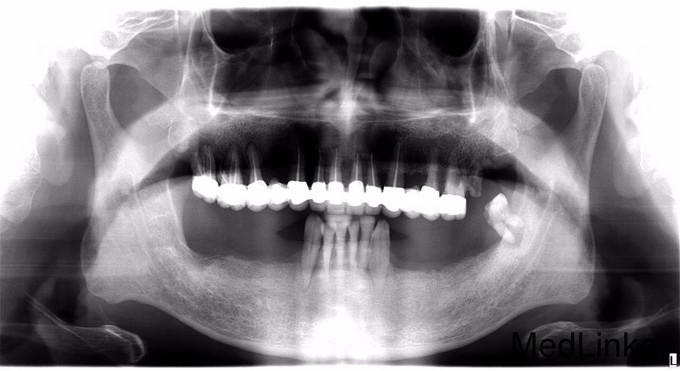

双侧下后牙拔除,无法咀嚼,要求修复

义齿修复下颌缺失牙